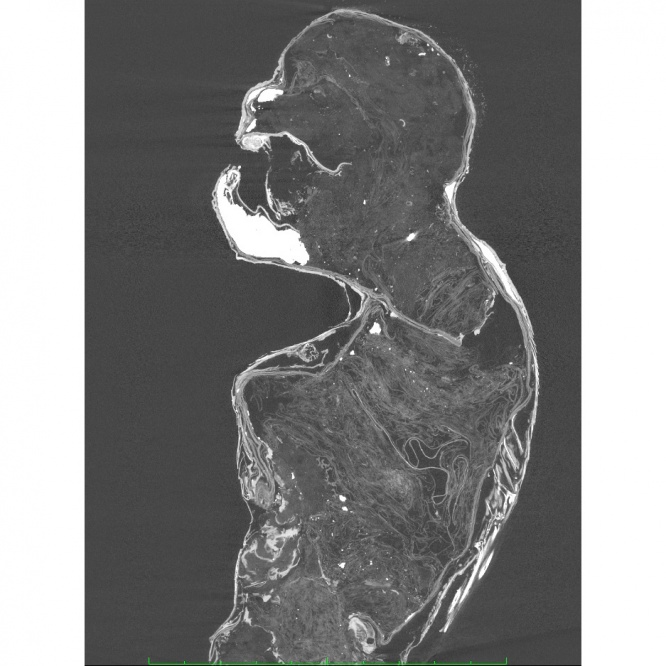

X線、X線CT撮影によるによる観察

木や金属の心材は無く、内部は布、紙、綿などからなる。

腕、肩、および首から頬にかけてフグ科魚類の皮が使われている。

背ビレ、尻ビレ、腹ビレの鰭条および鰭を支える担鰭骨、尾部骨格を確認することができた。

首の奥と下半身に金属製の針がある。